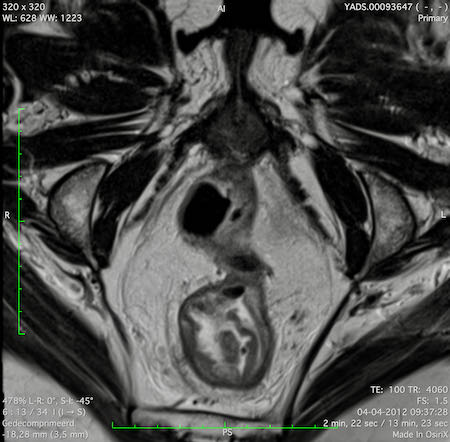

Hình ảnh

Các hình ảnh được cung cấp cho thấy ung thư biểu mô tế bào nhẫn với tình trạng dày lan tỏa thành trực tràng, hình ảnh bia bắn điển hình, và sự xâm lấn mỡ mạc treo trực tràng.